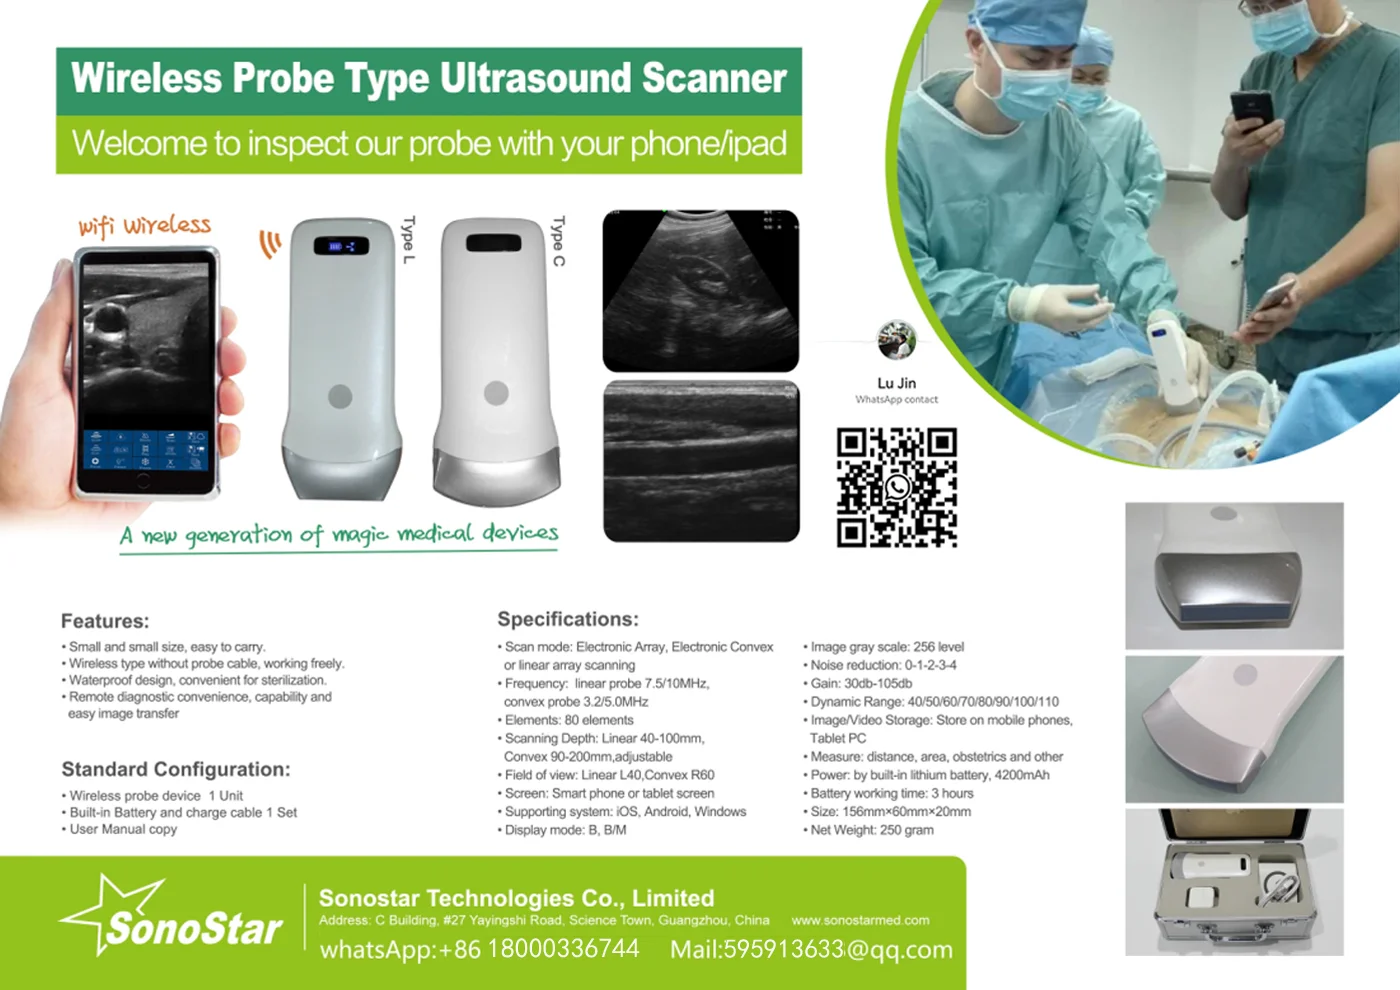

Linear Probe Parameters

-Scanning mode: Electronic array

-Display mode: B, B/M

-Probe element: 80

-Channel of RF circuit board: 16

-Frequency: 7.5MHz/10MH

-Scan depth: 20/40/60/100mm

-Head width: 40mm

-Image Adjust: BGain, TGC, DYN, Focus, Depth, Harmonic, Denoise, Color Gain, Steer, PRF

-Cineplay: auto and manual, frames can set as 100/200/500/1000

-Puncture assist function: the function of in-plane puncture guide line, out-of-plane puncture guide line, automatic blood vessel measurement.

-Measure: Length, Area, Angle, heart rate, Obstetrics

-Image save: jpg, avi and DICOM format

-Image frame rate: 18 frames / second

-Battery working time: 3~5 hours(according to different probe and whether keep scan)

-Battery charge: by USB charge or wireless charge, take 2 hours

-Dimension: 156×60×20mm

-Weight: 220g~250g

-Wifi type: 802.11g/20MHz/5G/450Mbps

-Working system: Apple iOS and Android, Windows 10 system

Standard Configuration:

-Main Host(probe) 1 Unit

-Internal Battery and charger 1 Set

-Non-slip lanyard

Convex Probe Pictures:

Linear Probe Pictures:

This machine can be used for both humans and animals: